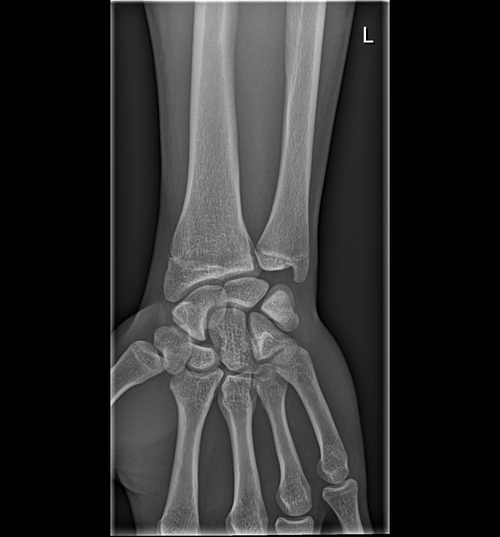

FYI. Im 17yr , 168cm ( 5'6) . my dad is 5'5 and mom is 5'2

the big doc said that my bone age is 17yr old and that my plates are closed but I trust org more then the doctors so here are my results.

is it worth to pin gh or should I accept it?